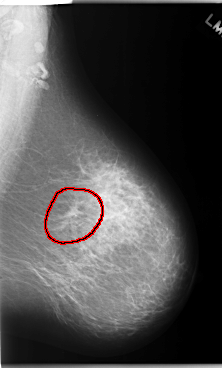

FILE: C_0173_1.LEFT_CC.OVERLAY TOTAL_ABNORMALITIES 1 ABNORMALITY 1 LESION_TYPE MASS SHAPE IRREGULAR MARGINS ILL_DEFINED ASSESSMENT 5 SUBTLETY 5 PATHOLOGY MALIGNANT TOTAL_OUTLINES 1 BOUNDARY |